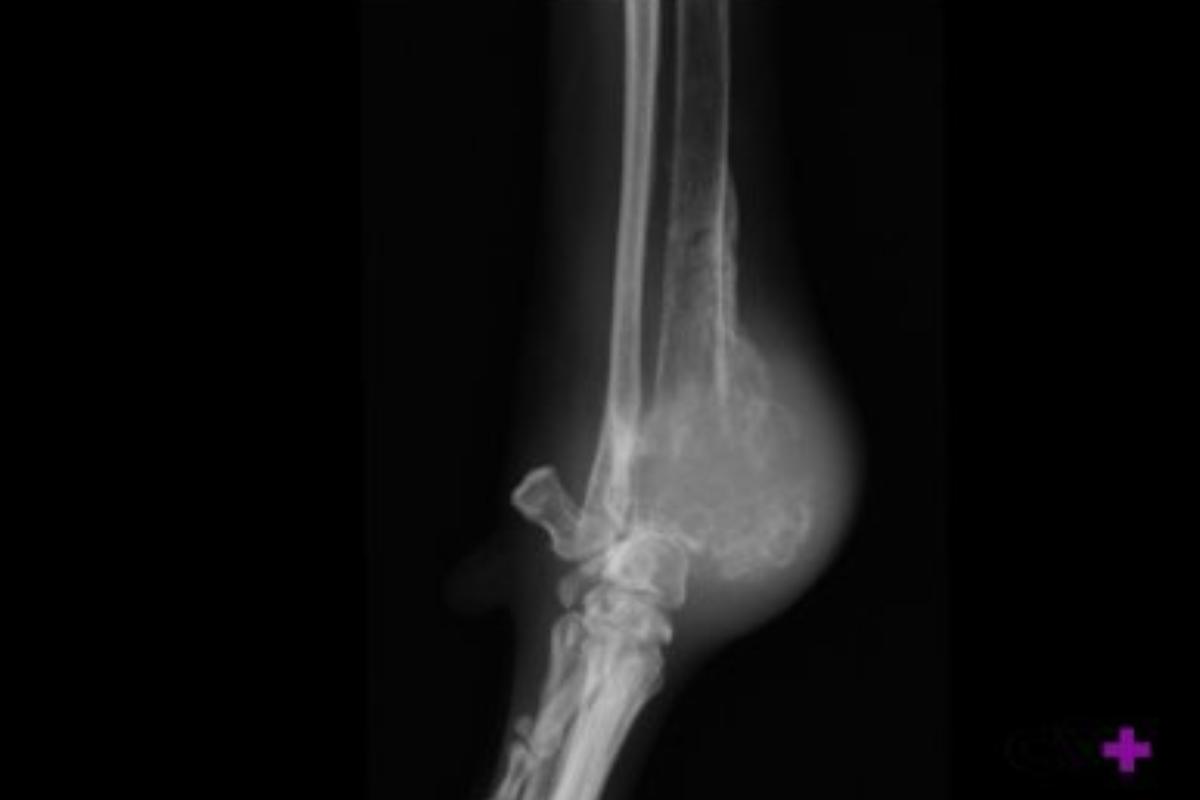

- Radiografía: las lesiones con una imagen de “apolillado”, con márgenes irregulares y mal definidos, especialmente cuando aparecen en las localizaciones más frecuentes de este tumor, nos hacen sospechar de la existencia de un osteosarcoma. Además, mediante la radiografía en ocasiones pueden observarse fracturas, puesto que un pequeño porcentaje de perros con osteosarcoma pueden presentar fracturas patológicas, es decir, fracturas originadas a raíz del daño óseo causado por el tumor. Cabe mencionar que las pruebas por imagen permiten realizar un diagnóstico presuntivo, pero para alcanzar el diagnóstico definitivo es necesario realizar las siguientes pruebas.